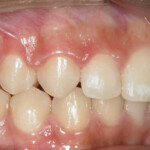

After Transformation!